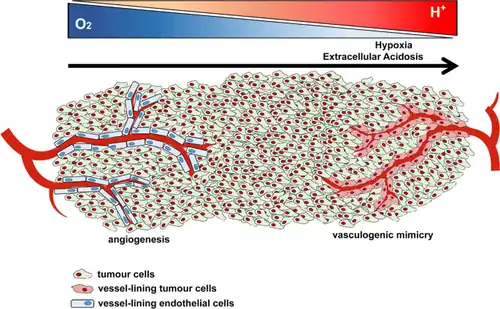

Vasculogenic mimicry (VM) is a strategy used by tumors to ensure sufficient blood supply is brought to its cells through establishing new tumor vascularization.[1][2][3] This process is similar to tumor angiogenesis; on the other hand vascular mimicry is unique in that this process occurs independent of endothelial cells. Vasculature is instead developed de novo by cancer cells, which under stress conditions such as hypoxia, express similar properties to stem cells, capable of differentiating to mimic the function of endothelial cells and form vasculature-like structures.[1][2] The ability of tumors to develop and harness nearby vasculature is considered one of the hallmarks of cancer disease development and is thought to be closely linked to tumor invasion and metastasis.[4] Vascular mimicry has been observed predominantly in aggressive and metastatic cancers and has been associated with negative tumor characteristics such as increased metastasis, increased tissue invasion, and overall poor outcomes for patient survival.[2][3] Vascular mimicry poses a serious problem for current therapeutic strategies due to its ability to function in the presence of Anti-angiogenic therapeutic agents. In fact, such therapeutics have been found to actually drive VM formation in tumors, causing more aggressive and difficult to treat tumors to develop.[5]

Vascular mimicry was first discovered in 1999 by Maniotis et al. who identified blood supplying channels in malignant melanoma that were composed entirely of tumor cell based structures. They found that cancer cells had taken on endothelial cell properties and were forming blood conducting vessels independent of normal angiogenesis pathways.[2] This finding spurred interest within the research community to discover the cause of this pathway and its relevance to disease.

Hypoxia and tumor microenvironment

Another major mechanism through which vasculogenic mimicry is induced is hypoxia. Hypoxia is very common in tumors due to insufficient vasculature to provide oxygen for the rapidly proliferating tumor issues within what is known as the tumor microenvironment.[16] To circumvent this problem, tumors utilize a diverse set of pathways to promote various angiogenesis strategies as well as vasculogenic mimicry. Hypoxia inducible factors (HIFs) are transcription factors which are able to remain functional during hypoxic conditions, bind to hypoxia responsive elements (HRE) on the genome. Gene targets with HRE sites bind HIF and mediate gene transcription.[16] The location of HRE sites on the genome varies among cancer cell types, however hypoxia based signaling has been found to activate VM related genes including VE-cadherin, COX-2, Twist, Nodal, EphA2, VEGF-A, and VEGR-1.[7] Hypoxia can also promote VM through other signaling pathways such as NF-κB, which upregulates Twist expression, an inducer of VM.[6] It is important to note as well that many chemotherapeutic agents used in the treatment of cancers intentionally drive hypoxia in tumors as a treatment strategy by inhibiting tumor angiogenesis. While these treatments vary in efficacy depending on cancer type and patient, it has been shown that such therapies may actually drive tumors down more aggressive routes through the promotion of VM based tumor survival.[9]

Melanoma is an aggressive skin cancer which has been shown to utilize both angiogenesis and vascular mimicry to drive metastasis and also increase treatment resistance.[1] Metastatic melanoma has very poor survival outcomes with a median survival of 6 months.[19] VM has been identified to be present only in metastatic and very aggressive melanomas. Major biomarkers of VM in melanoma include: VEGF-A, HIF-1A, and Nodal.